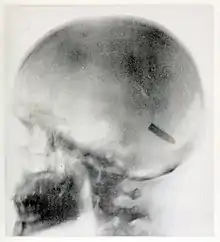

On August 20, 1899, she took one of her most famous radiographs, an image showing a Mauser 7 mm bullet lodged in the brain of John Gretzer Jr., in the region of the left occipital lobe.[12][15] Private Gretzer, of the 1st Nebraska Volunteers, wounded at Mariboa, Philippines on 27 March 1899 during the Spanish–American War. The private later returned to duty as a mail clerk.[16] Accounts of the case were reported in the 1902 edition of The International Text-Book of Surgery and in newspapers.[17] Another case of a bullet lodged in a soldier's skull, X-rayed by Fleischman was also reported in newspapers in 1899.[18]